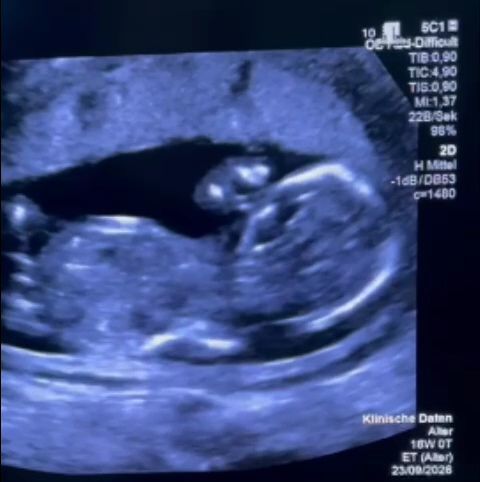

O femeie însărcinată din România, diagnosticată cu o malformație minoră la făt, a fost supusă unui tratament medical inacceptabil la un spital din București, potrivit relatărilor fostului secretar de stat în Ministerul Sănătății, MONICA ALTHAMER. Gravida a fost sfătuită să amâne intervenția medicală, în ciuda recomandărilor urgente venite din partea unui medic german. În final, intervenția a fost efectuată în Germania, iar specialiștii au criticat lipsa de consiliere din România.

Povestea începe în săptămâna a 12-a de sarcină, când femeia a aflat despre malformația minoră a fătului. Exista un tratament disponibil, însă, în loc să primească sprijin și informații clare, părinții s-au confruntat cu o serie de obstacole. Au ales Spitalul Filantropia din București pentru tratament, dar au fost dezamăgiți de modul în care au fost tratați. Au raportat un tratament degradant și lipsa informațiilor esențiale.

Medicii le-au recomandat să amâne procedura, chiar dacă un specialist german insista asupra urgenței. Când au solicitat documente pentru a putea beneficia de tratament gratuit în străinătate, cererea le-a fost respinsă. În cele din urmă, au reușit să ajungă în Germania, unde intervenția a fost efectuată cu succes de un medic german. Acesta a calificat consilierea primită în România drept „extrem de slabă”.